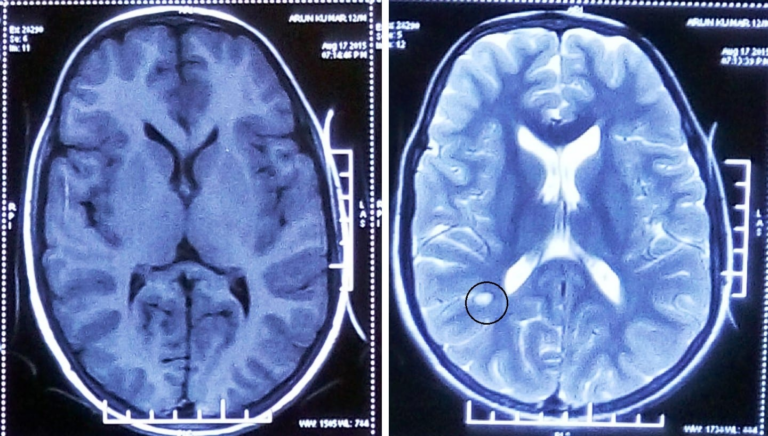

Посмертне дослідження тканин американця, який загинув від ПСПЕ – рідкісного, але небезпечного ускладнення кору, – дало змогу відтворити картину поширення…